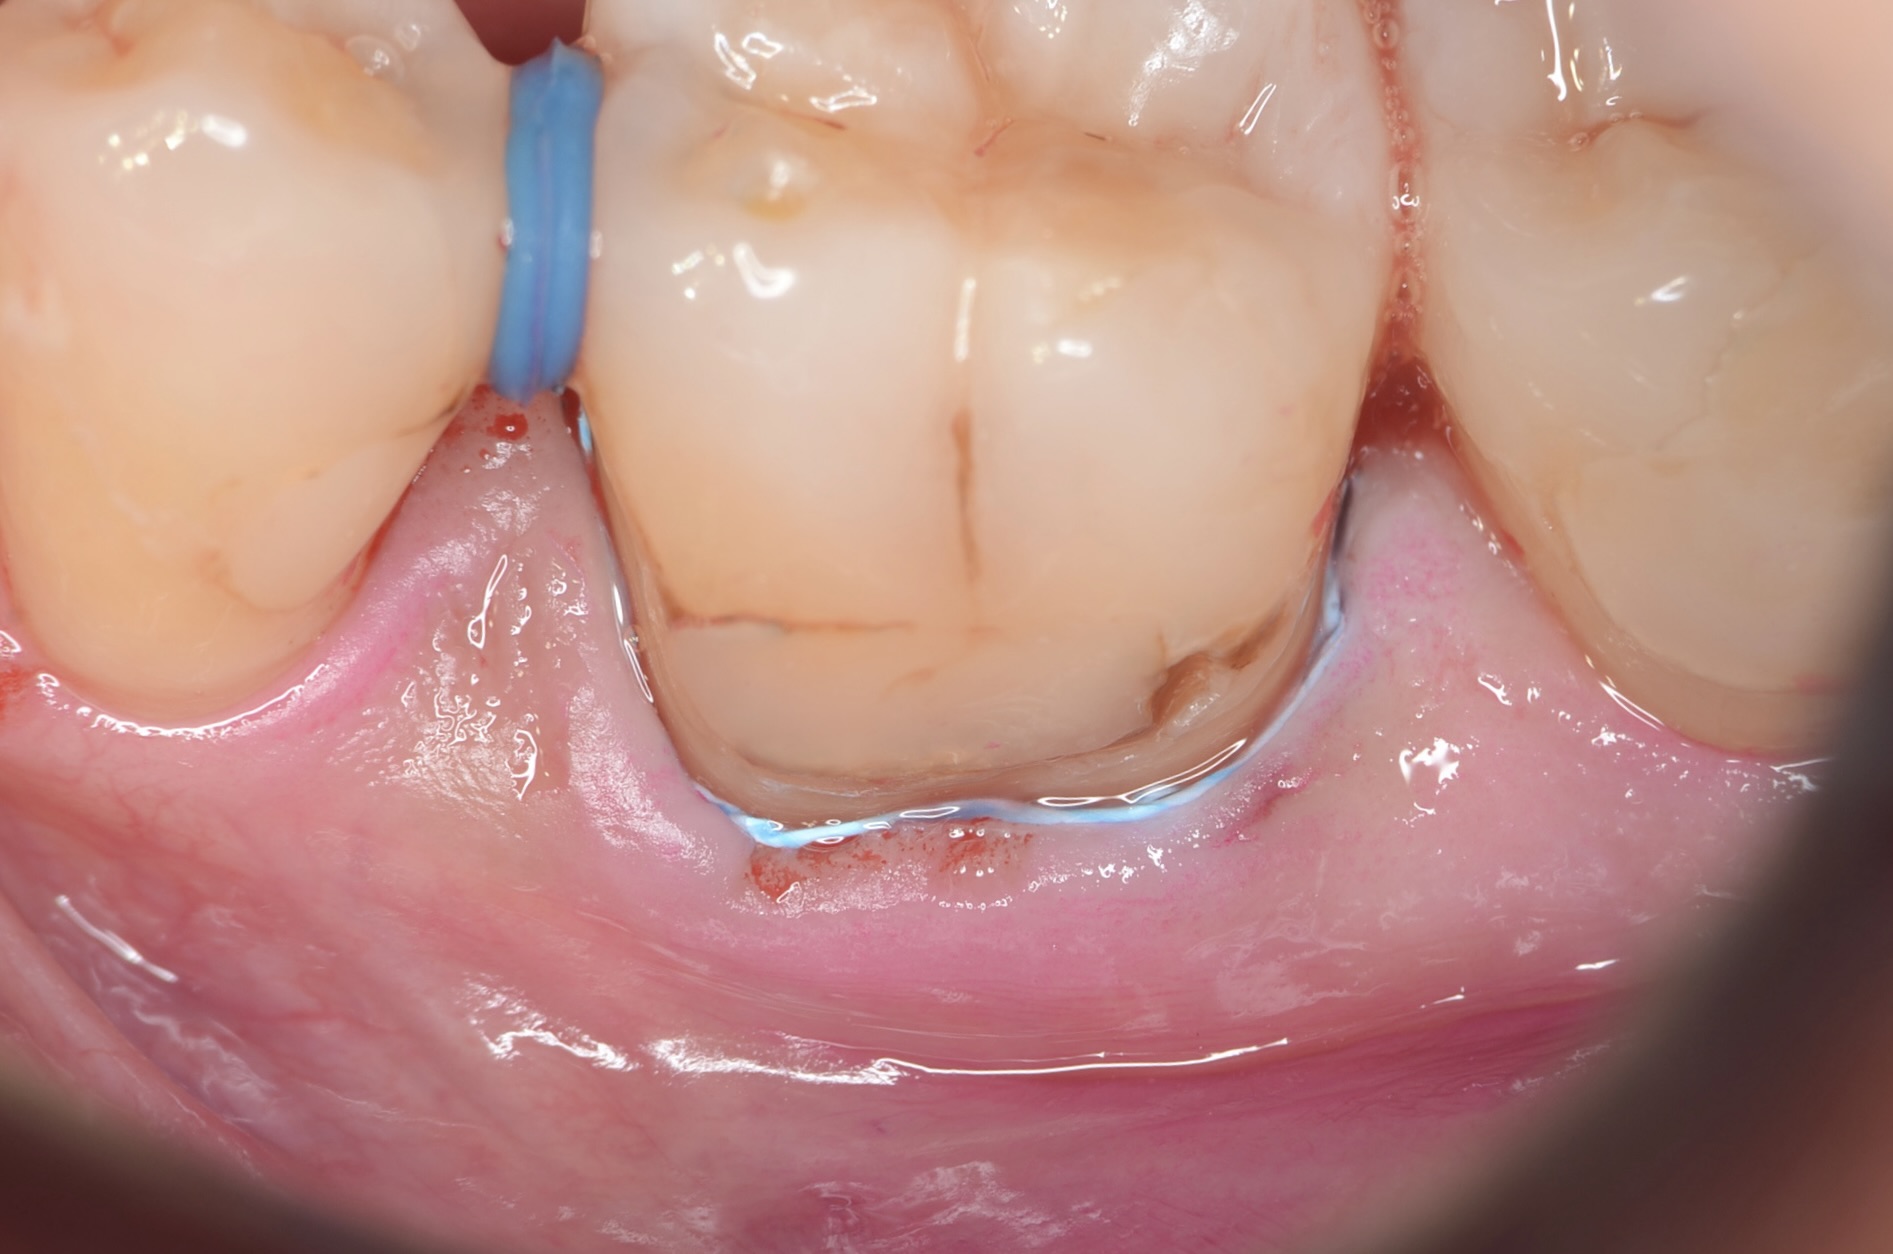

テフロンテープにより歯肉圧排

青色のテフロンテープを紐状にしたものを歯肉溝に挿入しました。レジンが、ラバーダムに触れないようにするためです。 -